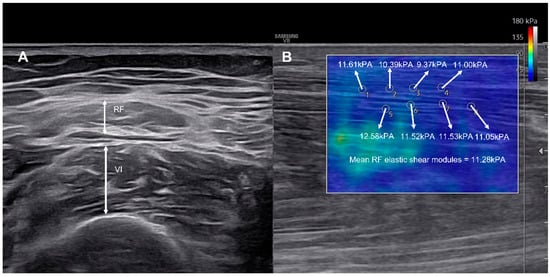

Muscle thickness was recorded to the nearest 0.01 cm using electronic calipers. Shear-wave elastography was used to assess viscoelastic properties, with the probe aligned longitudinally along the muscle fascicles [22]. A circular region of interest (ROI, 1 mm diameter) was placed at the mid-belly of each muscle, and the mean value of eight ROIs was calculated as the elastic shear modulus (kPa) [10,23] (Figure 1). Each measurement was performed twice by the same experienced operator, and the average value was used for analysis to ensure intra-rater reliability.

Figure 1. Representative ultrasonographic images showing measurement of RF and VI muscle thickness (A), and corresponding shear-wave elastography map (B). The color scale indicates the elastic shear modulus (kPa) ranging from 0 to 180 where blue represents softer tissue and red indicates stiffer tissue. Multiple regions of interest (ROIs) were positioned along the muscle fascicles, and mean shear modulus was automatically calculated by the system.